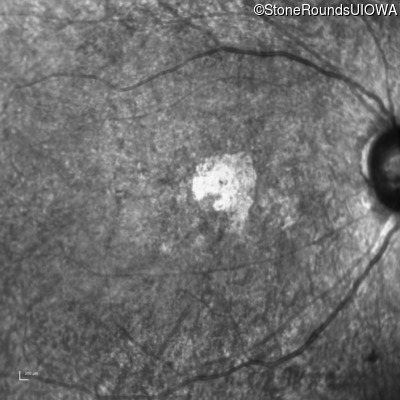

The clinical features supporting the diagnosis of Bardet Biedl syndrome in this patient include: bone-spicule-like pigmentation, narrowed arterioles and macular atrophy on ophthalmoscopy; photoreceptor loss on OCT; ulnar polydactyly, obesity, abnormal cognition, hypertension; and, normally sighted parents.